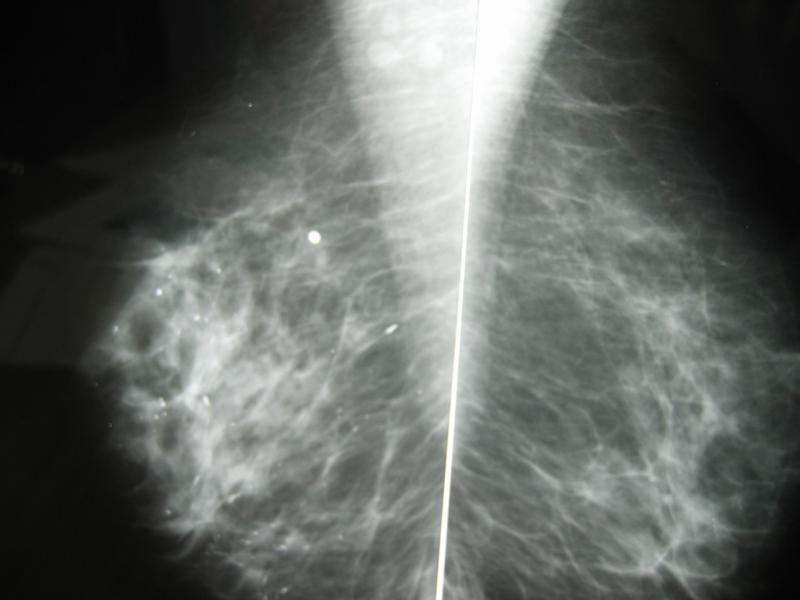

O exame mais eficaz no rastreamento do câncer de mama é a mamografia.

A recomendação da Sociedade Brasileira de Mastologia é para que toda mulher com mais de 40 anos realize este exame anualmente.

A mamografia quando realizada anualmente em mulheres com mais de 40 anos, tem a capacidade de reduzir a mortalidade por câncer de mama na ordem de 20 a

30%.